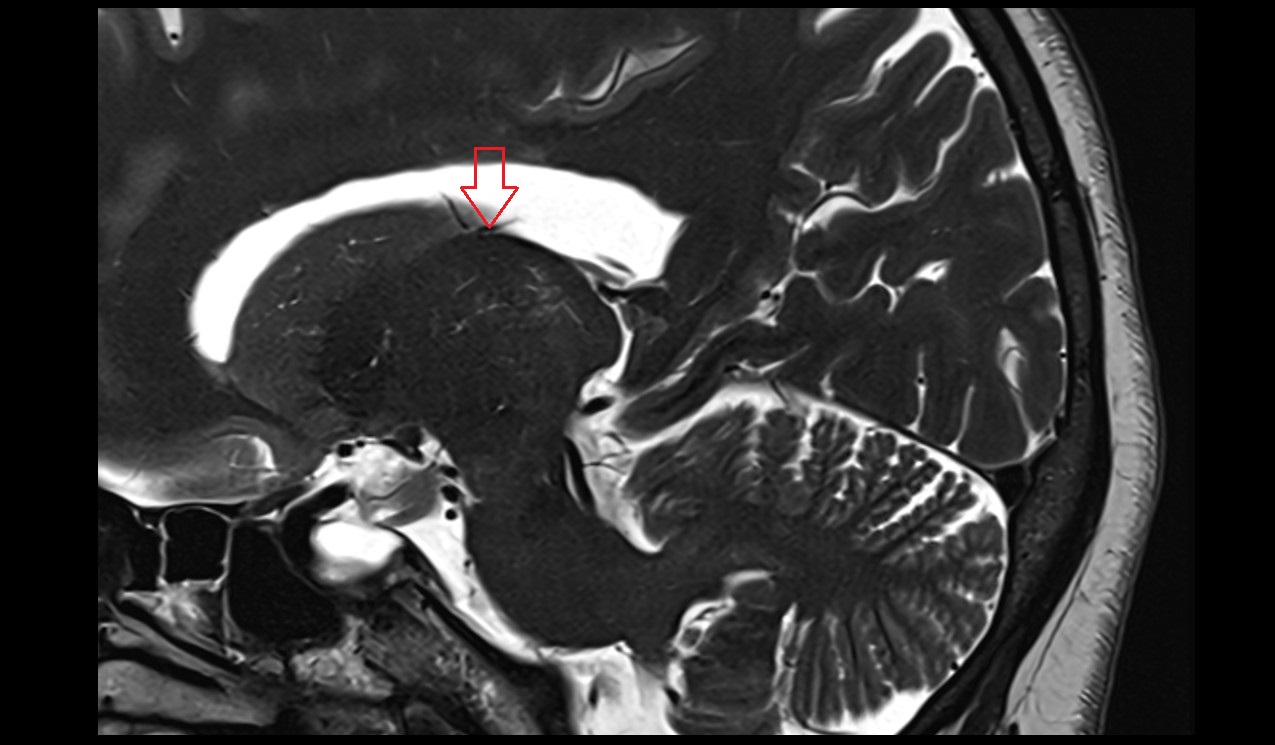

- Fetal brain

- Fetal lateral ventricle